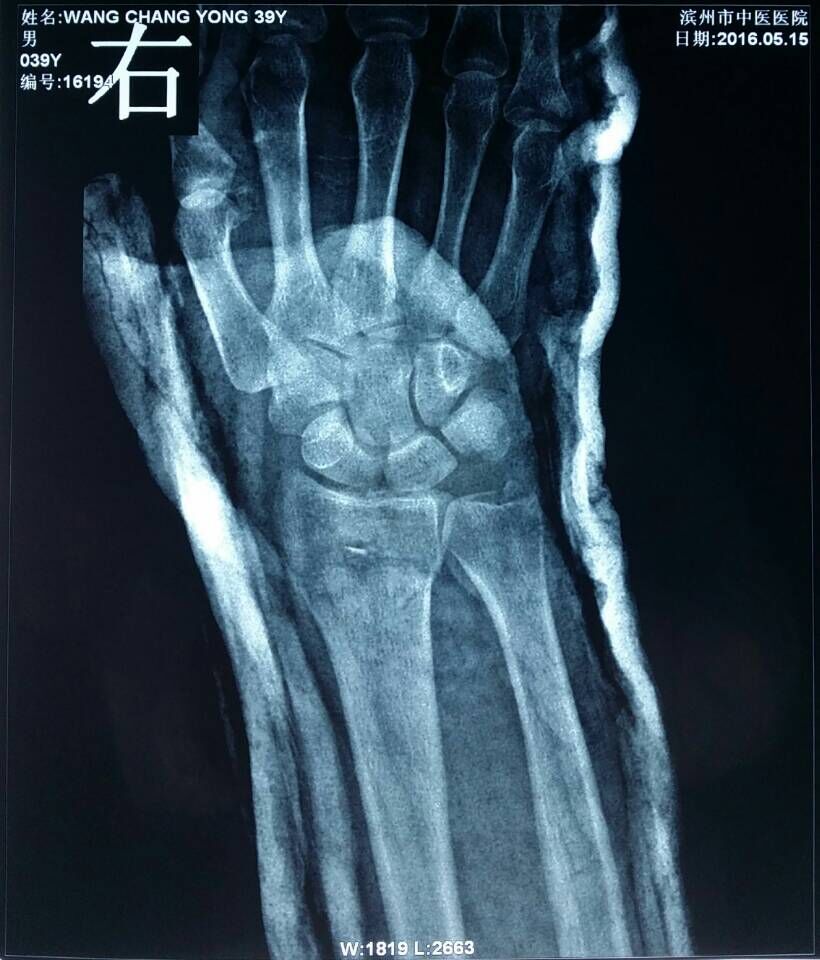

患者王某,男,39岁,踢足球时摔伤右腕关节,右腕部肿胀疼痛、活动受限2小时来我院骨伤科就诊。骨伤科刘陆勇大夫及时安排患者进行X片拍照,X-ray片(图1,2)示:右桡骨远端骨折,远端向桡侧、背侧移位,近端向掌侧移位,右端尺骨茎突骨皮质不连续,见游离骨片影,初步诊断为“桡骨远端骨折”。在确定骨折损伤程度后,刘陆勇大夫和杨晓晓大夫采用中医传统整复手法,给予患者行手法整复石膏外固定,整复后患者再次行x-ray检查(图3,4),x线片显示复位情况良好,效果显著。此次治疗使患者避免切开手术及二次手术取内固定的痛苦,最大限度地减轻了病人的经济负担,受到了病人的一致好评。